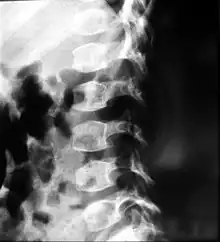

X-ray of the spine in a patient with spondyloepimetaphyseal dysplasia